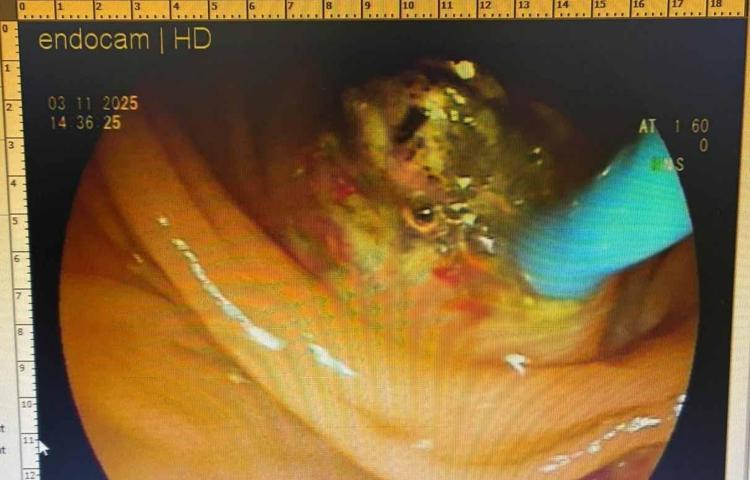

Karın ağrısının ise safra kesesindeki taşlardan olduğu belirlenen Evin Aslan, ameliyata alındı. Hastanın iç organlarının ters yönde bulunmasının dünyada nadir görülen bir durum olduğunu söyleyen doktor Akbay, "Hastamız için özel oda ve cihazlarımızı dizayn ederek, ERCP yöntemiyle müdahale ettik. Hastamız iç organlarının ters yönde olması gerekçesiyle uygulanan ERCP yönteminde dünyadaki 48’inci hasta oldu. 47’nci hasta daha önce Diyarbakır’da bu yöntemle sağlığına kavuşmuştu" diye konuştu.

Vücudunda ters yönde bulunan safra kesesinden ameliyata alındığını söyleyen uzman doktor Akbay, “Hastamız karın ağrısı şikayetiyle hastanemize başvurdu. Çekmiş olduğumuz MR'da karın iç organlarının tam tersi yerleşmiş olduğunu gördük. ‘Situs inversus totalis’ denilmektedir buna. Sağda olması gereken karaciğer ve safra kesesi sol tarafta, solda olması gereken kalp ise sağ tarafta yerleşmişti.

Bu hastamızın safra kanalında taşı olup, akut pankreatit atağı geçirmekteydi. Safra kanalındaki taşlarını ileri endoskopik yöntem olan ERCP işlemiyle başarılı bir şekilde ameliyat ettik" ifadelerini kullandı.

Hastadaki durumunun dünyada ender görüldüğünü söyleyen doktor Akbay, "Hem organların ters tarafta olması, aynı zamanda safra kanalında taş ve pankreklatları geçirmesi çok nadir görülen bir durumdur. Dolayısıyla ileri endoskopik yöntem olan ERCP işlemi içinde hastanın tam ters pozisyonda, başarılı bir şekilde yatırdık. Odanın dizaynını ona göre ayarladık, işlem oldukça zor olmasına rağmen başarılı bir şekilde işlemimizi yaptık, hastamız sağlığına kavuştu" diye konuştu.